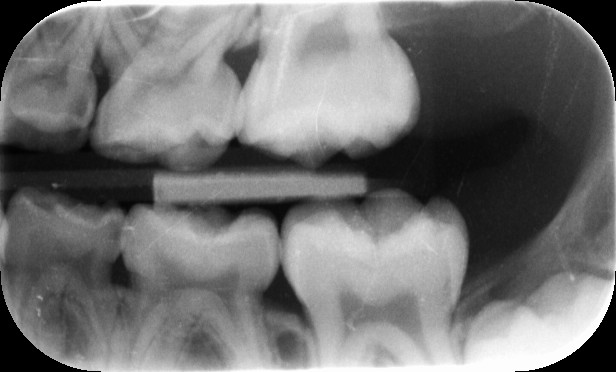

Nu is er bij de laatste controle foto`s gemaakt en daar zijn volgens de tandarts 6 gaatjes te zien en die moeten volgens haar allemaal gevuld worden.

Ik heb de foto`s opgevraagd en kan als ik heel erg m`n best doe 1 gaatje vinden (ik ben dan ook geen tandarts).

Wat kunnen jullie van de foto`s zeggen?

Kunnen jullie mij vertellen waar de gaatjes zitten of hoe ik ze herken? Voor mij is alleen het gaatje op de bovenste foto aan de rechter zijde van de middelste kies herkenbaar.

Op de bovenste foto's zie ik minstens 3 flinke cariessen, mogelijk nog een beginnende en een twijfelachtige vulling. Op de onderste minstens 2 duidelijke cariessen.Thv de caries zie je een opklaring of radioluscentie, zoals dat dan heet .Hoe je dit herkent? Radiodiagnostiek hoort bij het vakgebied van de tandarts, ik denk dat dit forum hier niet voor bedoeld is.